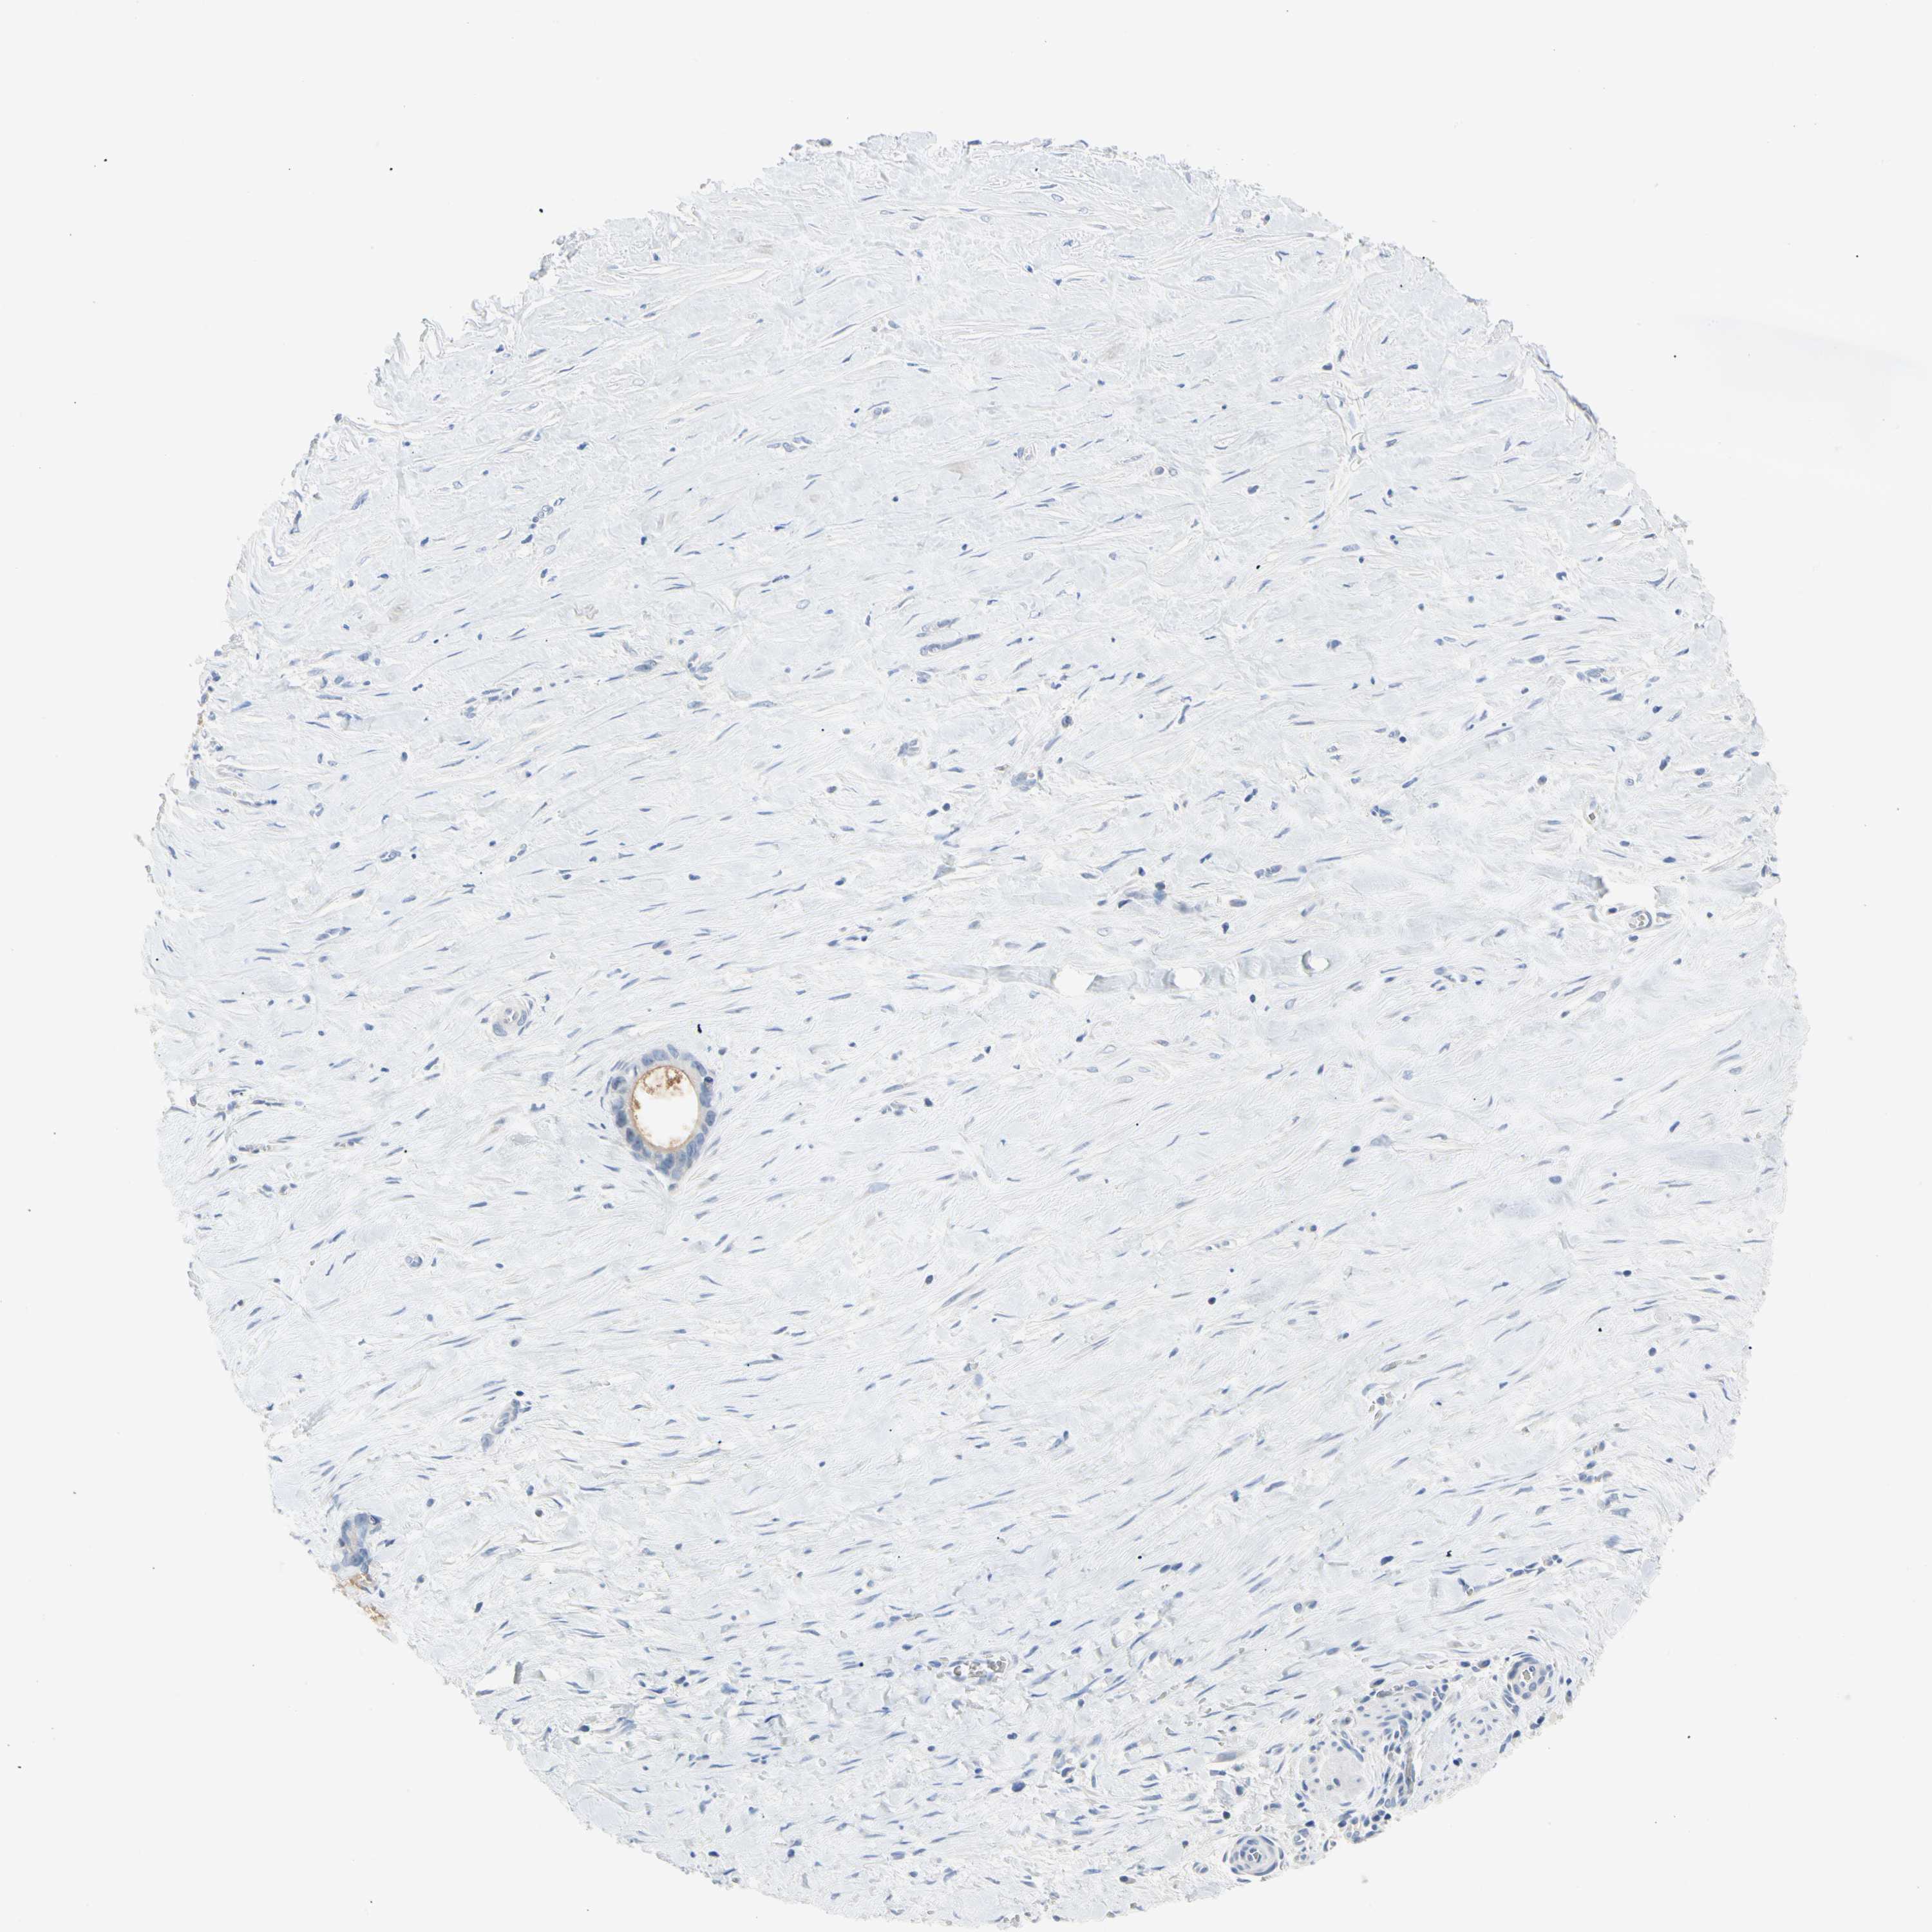

LIVER CANCER - Protein expressioni

A mouse-over function shows sample information and annotation data. Click on an image to view it in a full screen mode. Samples can be filtered based on level of antibody staining by selecting one or several of the following categories: high, medium, low and not detected. The assay and annotation is described here.

Note that samples used for immunohistochemistry by the Human Protein Atlas do not correspond to samples in the TCGA dataset.

Antibody stainingi

Antibody staining in the annotated cell types in the current human tissue is reported as not detected, low, medium, or high, based on conventional immunohistochemistry profiling in selected tissues. This score is based on the combination of the staining intensity and fraction of stained cells.

Each image is clickable and will lead to virtual microscopy that enables deeper exploration of all samples and also displays staining intensity scores, fraction scores and subcellular localization as well as patient and tissue information for each sample.

Antibody HPA007421

Antibody HPA008061

Staining

High

Medium

Low

Not detected

Intensity

Strong

Moderate

Weak

Negative

Quantity

>75%

75%-25%

<25%

None

Location

Nuclear

Cytoplasmic/membranous

Cytoplasmic/membranous,nuclear

Cholangiocarcinoma

Carcinoma, Hepatocellular, NOS